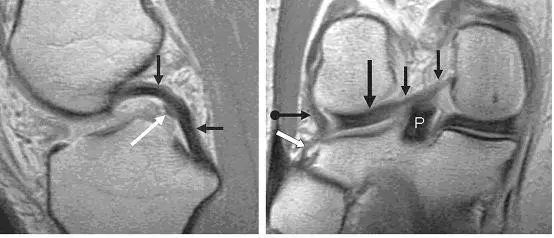

图 2 正常半月板

左图:外侧半月板,由于横截面面积一致,故在MRI 上可见外侧半月板前后角(纵向白色箭头)形状和大小较相似。上下腘肌半月板纤维束(黑色箭头)在外侧半月板后角处,形成裂孔,中间有腘肌腱(水平白色箭头)通过。右图:内侧半月板,可见后角(白色圆箭头),略大于前角(白色直箭头)